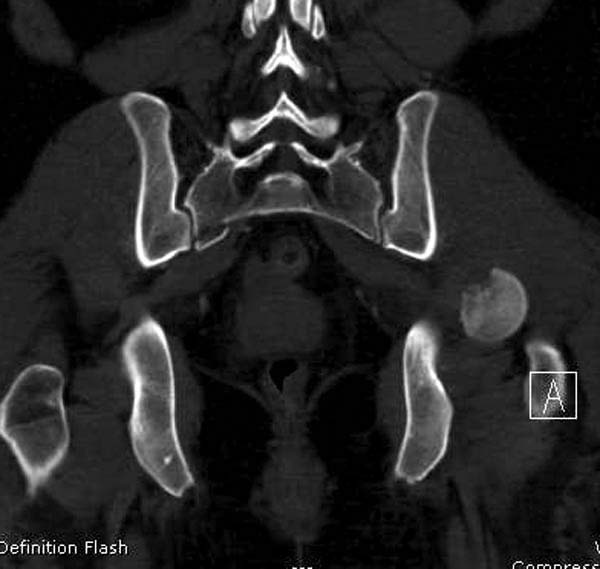

В диагноз еще необходимо внести закрытую (?) ротационно-нестабильную травму таза с переломами лонных седалищных костей, боковой массы крестца справа.

Перелом позвоночника и боковую компрессию таза отнесли к стабильным переломам и не стали форсировать события до лучших времен...

После спадения отека на стопе произведена фиксация тарана. Кстати, коллеги пересмотрели первоначальную консультацию по позвоночнику и на двух уровнях провели фиксацию. Из-за длительного постельного режима без нагрузки таз не стали оперировать...